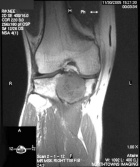

J.O. - 23 year old white male with right knee pain for several years

Zoom image: Radiological image Radiological image.